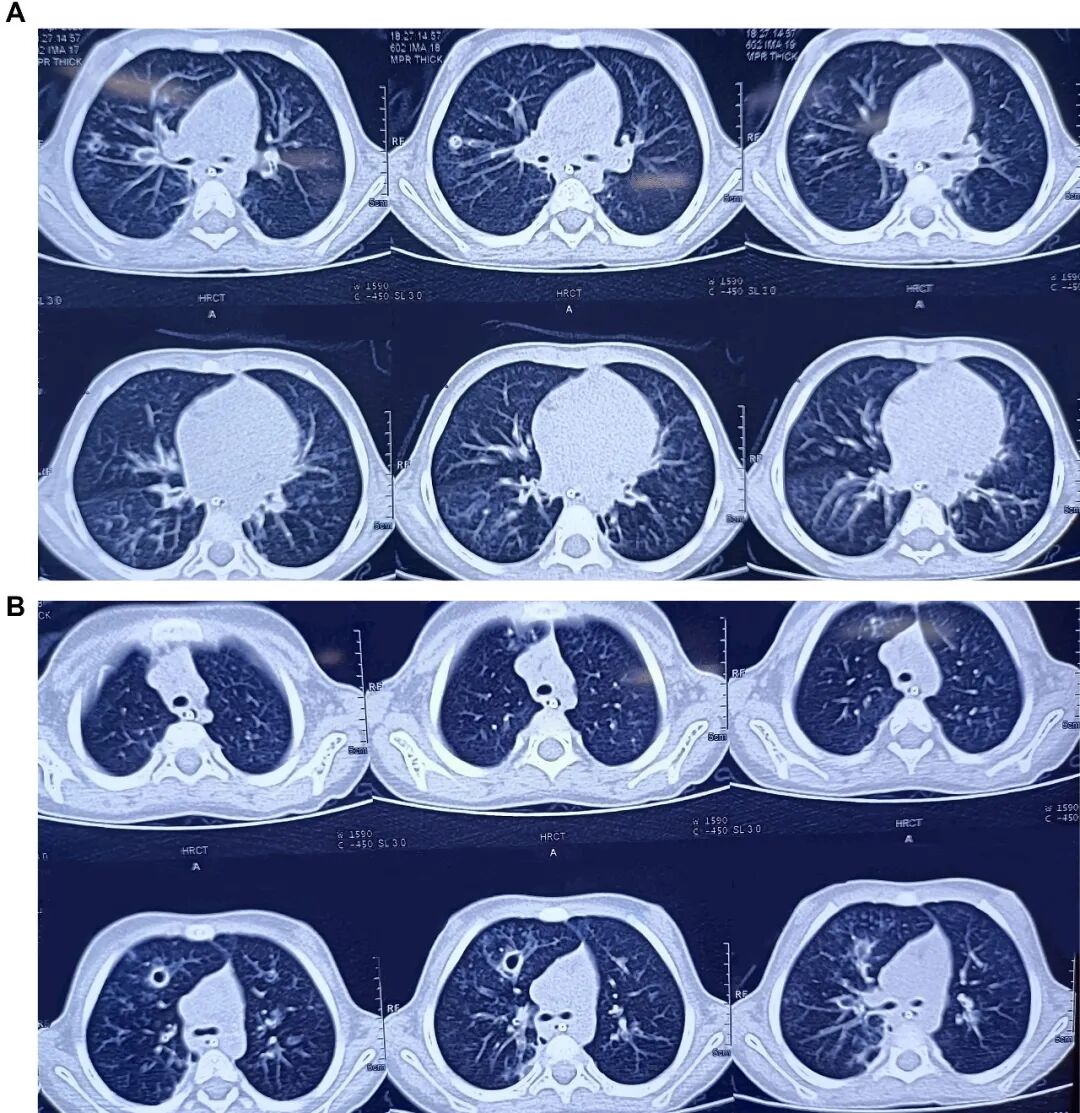

胸片显示双肺野过度充气,伴右肺中野不均匀浸润影及支气管壁增厚(图1)。胸部高分辨率CT扫描显示右肺上叶前段可见厚壁囊腔,可能存在交通,紧邻管壁明显增厚的亚段支气管——提示囊性支气管扩张(图2)。免疫功能缺陷检查已排除:HIV报告正常,免疫球蛋白谱正常,淋巴细胞亚群分析正常。IgA=54.67 mg/dL,IgG=990.32 mg/dL,IgM=404.186 mg/dL,IgE=16.3 IU/mL,CD3(T细胞)=2237.32 个/μL ,62.85% ;CD4 TH细胞=1165.21 个/μL ,32.73% ;CD8 T细胞=1065.26 个/μL,29.92%;CD4/CD8比值1.09均处于正常范围

2.A,胸部高分辨率CT扫描显示左右肺囊性支气管扩张,伴有空穴病变。B,胸部高分辨率CT扫描显示右肺上叶前段有厚壁囊性腔体,并有囊性支气管扩张的证据。